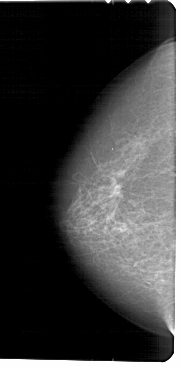

A_1457_1.LEFT_MLO

LEFT_CC LINES 5491 PIXELS_PER_LINE 2686 BITS_PER_PIXEL 12 RESOLUTION 43.5 NON_OVERLAY